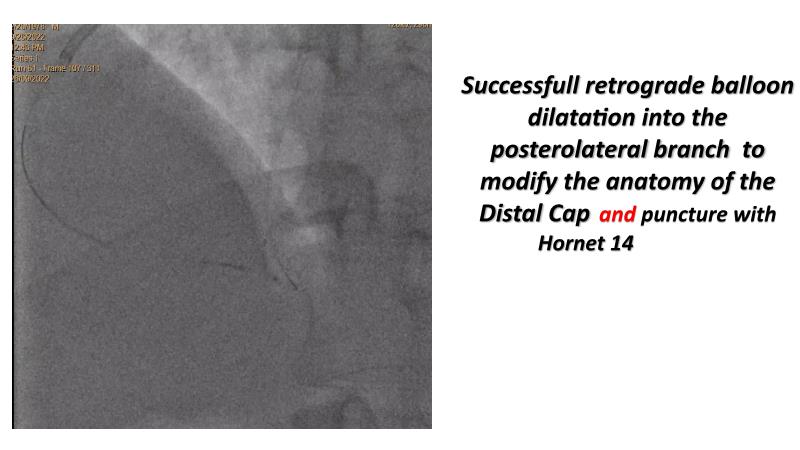

Thanks to the recorded complex CTO case shared in this session, learn how to perform ultra-low contrast PCI, learn what skills are required and tools available to perform ultra-low contrast coronary interventions in CTO, and become aware of the importance of relying on less contrast injections to guide PCI in complex CTO cases.